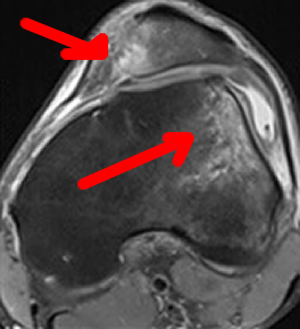

Intéret de l'IRM

Elle va montrer la trace indirecte de la luxation avec un oedeme osseux (l'os est gris blanc- sur le côté du fémur, où la rotule est venue taper lors de la luxation. Cette image persiste environ 6-8 semaines après l'épisode. Il est donc important de faire cette IRM.

Lorsque l'aileron interne est distendu ou rompu, la radio de profil du genou en extension, quadriceps contracté, montre la rotule presque de face, preuve de sa rotation.

C'est l'intervention de base, la plus souvent utilisée pour stabiliser la rotule. Sa meilleure indication : si rotation externe importante de la rotule en extension, bien visible sur une radio debout, de profil avec le quadriceps contracté (photo ci-dessus).